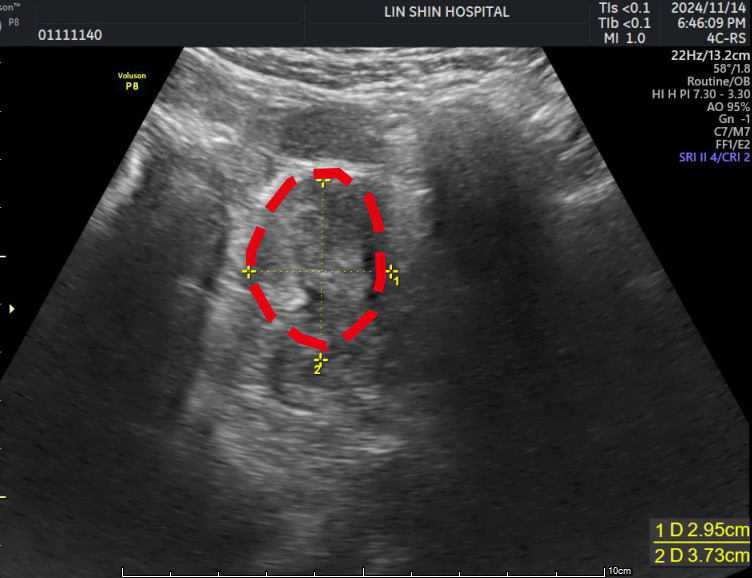

〔記者蔡淑媛/台中報導〕52歲的徐小姐長年經痛、頻尿、夜尿及下腹悶脹等症狀 去年檢查發現子宮前壁長有一顆約7公分大,有如中型芒果大小的子宮肌瘤,已經壓迫膀胱,選擇「子宮肌瘤微波消融術」治療,住院兩日後出院,肌瘤逐漸縮小到只剩1顆小番茄大,症狀也大幅改善。

胡洺褘指出,患者希望保留子宮,並考量恢復期短、疼痛感較低,決定接受自費的子宮肌瘤微波消融術,該手術透過影像導引,將微波能量精準作用於肌瘤組織,使肌瘤壞死並逐漸被人體吸收,屬於微創治療方式。